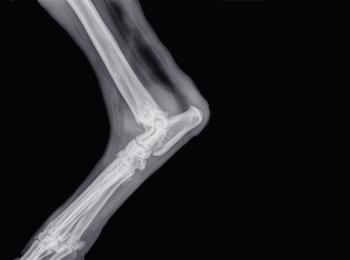

Beautiful, a 12-year-old mixed breed, jumping over a temporary fence led her to a severe injury and rehabilitation